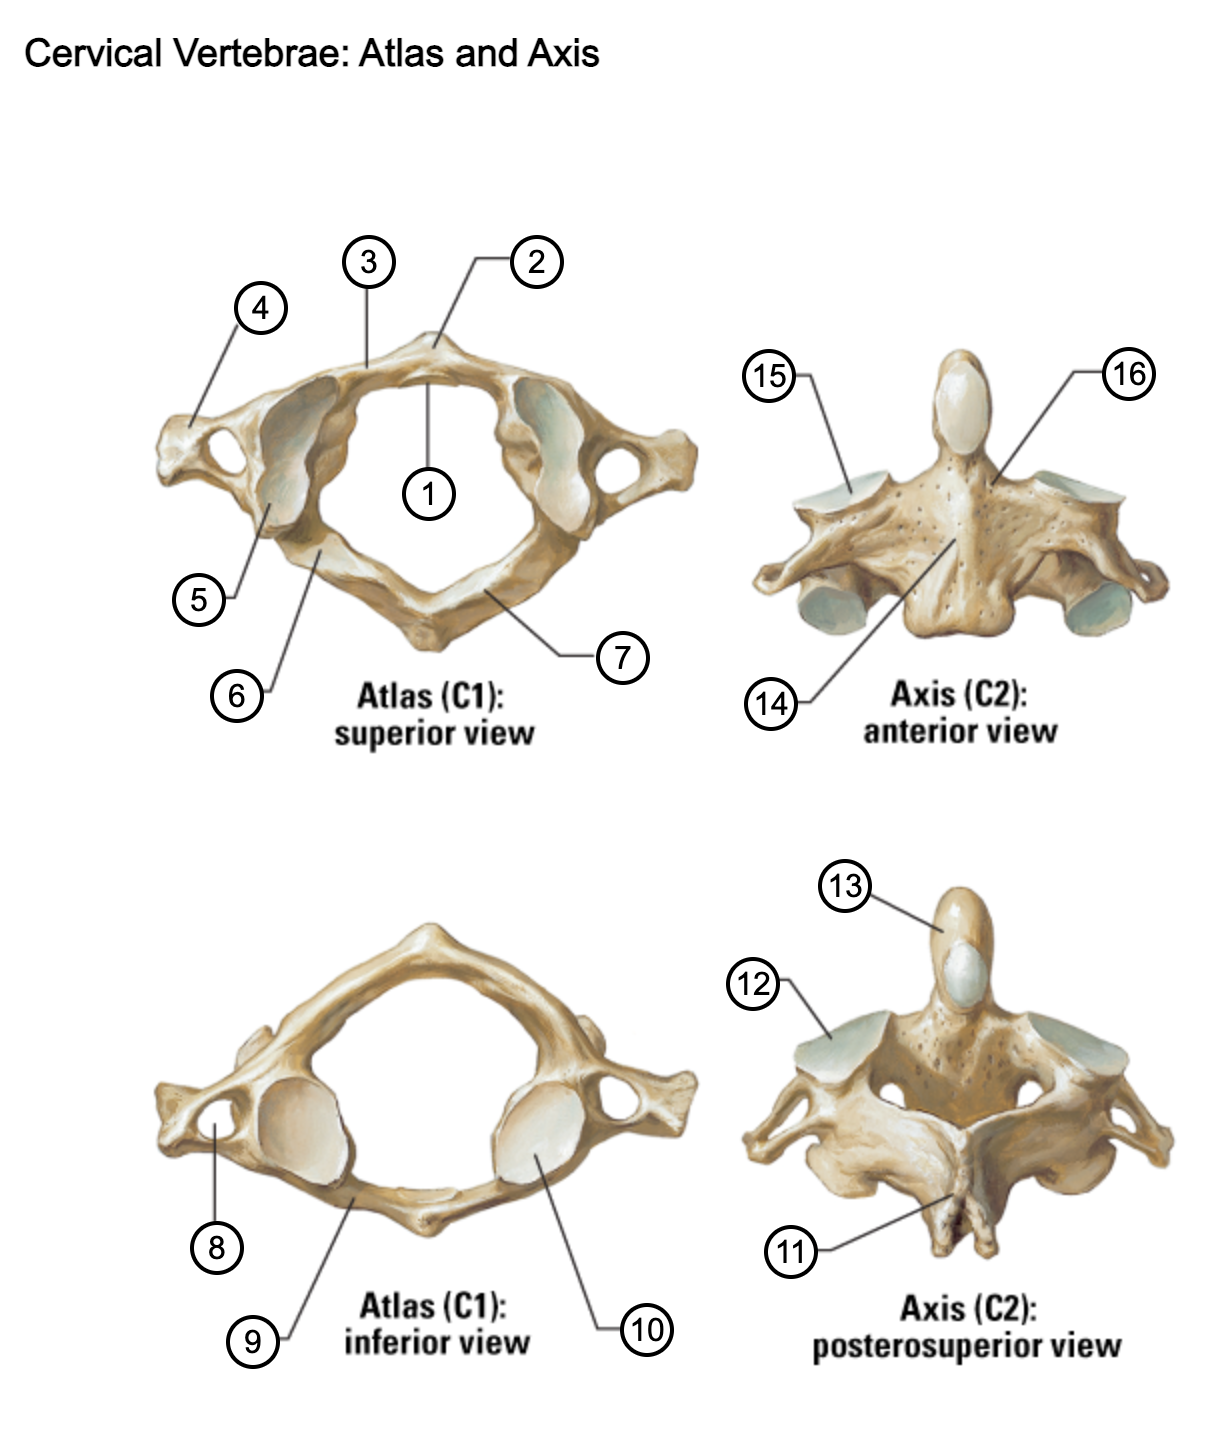

1

facet for dens

2

anterior tubercle

3

anterior arch

4

transverse process

5

superior articular surface of atlas

6

groove for vertebral artery

7

posterior arch

8

transverse foramen

9

anterior arch

10

inferior articular surface of atlas

11

spinous process

12

superior articular facet

13

dens of axis

14

body of axis

15

superior articular facet for atlas

16

pedicle of vertebral arch